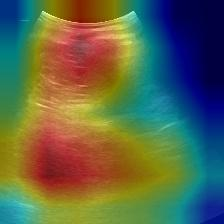

Most deep neural networks (DNNs) based ultrasound (US) medical image analysis models use pretrained backbones (e.g., ImageNet) for better model generalization. However, the domain gap between natural and medical images causes an inevitable performance bottleneck. To alleviate this problem, an US dataset named US-4 is constructed for direct pretraining on the same domain. It contains over 23,000 images from four US video sub-datasets. To learn robust features from US-4, we propose an US semi-supervised contrastive learning method, named USCL, for pretraining. In order to avoid high similarities between negative pairs as well as mine abundant visual features from limited US videos, USCL adopts a sample pair generation method to enrich the feature involved in a single step of contrastive optimization. Extensive experiments on several downstream tasks show the superiority of USCL pretraining against ImageNet pretraining and other state-of-the-art (SOTA) pretraining approaches. In particular, USCL pretrained backbone achieves fine-tuning accuracy of over 94% on POCUS dataset, which is 10% higher than 84% of the ImageNet pretrained model. The source codes of this work are available at https://github.com/983632847/USCL.